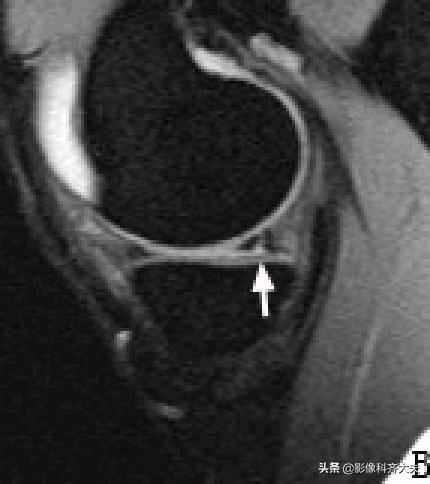

内侧半月板后角上隐窝: